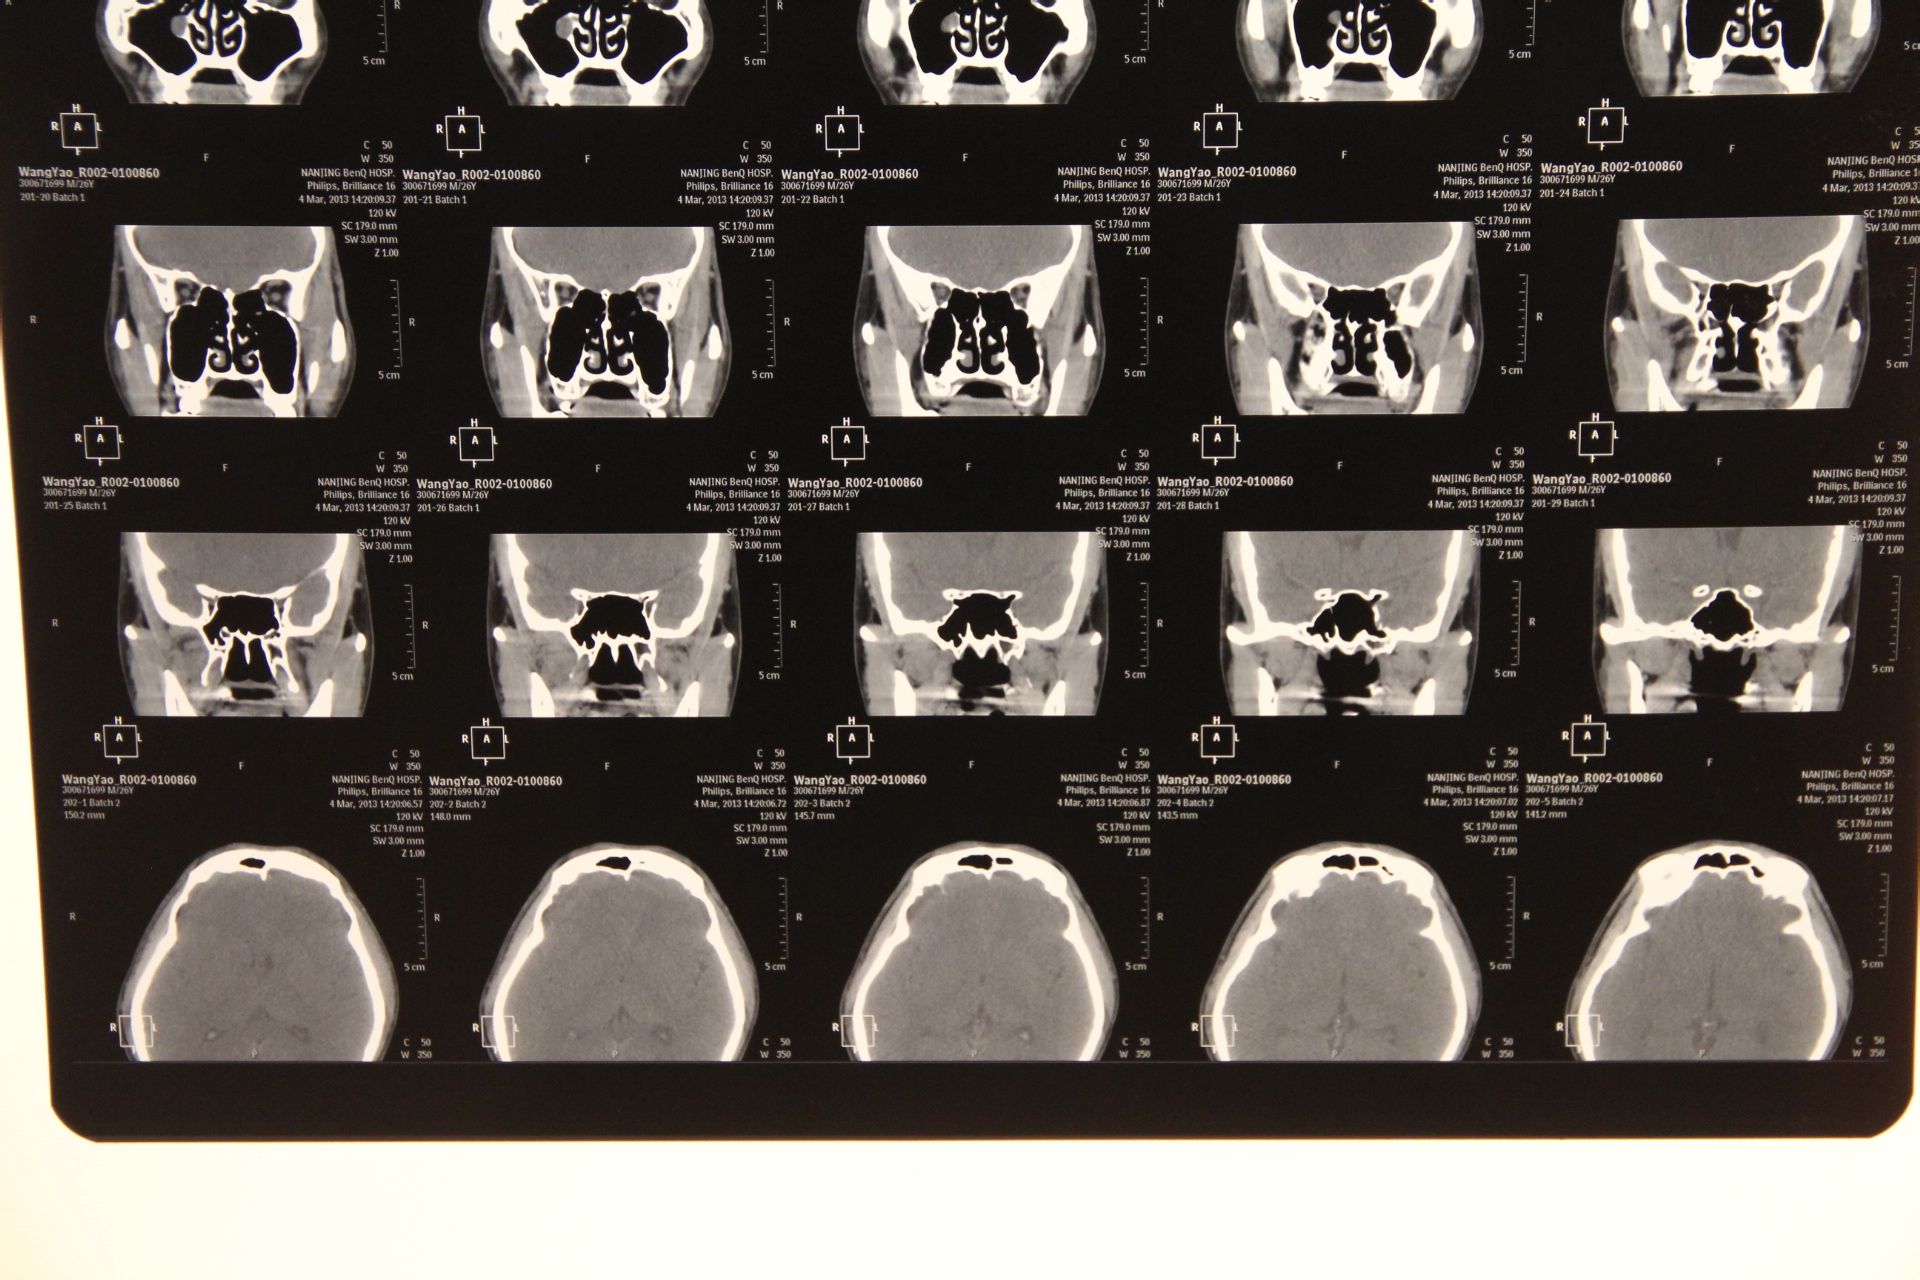

帮我看下这个ct图片,上颌窦里面有东西.现在鼻子很不舒服.

鼻窦ct检查显示, 张先生两侧上颌窦都有囊肿, 特别是左侧上颌窦窦腔内

看看上颌窦是什么?